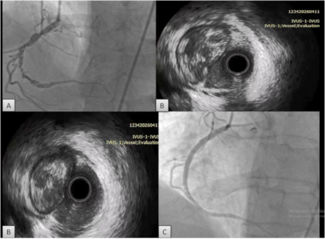

A 59-year-old man was referred to our institution for potential MitraClip (Abbott Vascular) therapy after he was found to have severe mitral regurgitation (MR) seen on transthoracic echocardiography. He had a history of coronary artery disease and functional MR, and underwent coronary artery bypass grafting and mitral annuloplasty (28 mm CG Future; Medtronic Inc.) 4 years prior at an outside institution. A permanent pacemaker was also implanted for advanced atrioventricular block. The procedure was complicated by a methicillin-resistant  staph aureus sternal wound infection requiring multiple debridements and wound vacuum drainage for 1 year. There was no documented bacteremia at that time. Three years later, he had several admissions for decompensated heart failure, volume overload, and pulmonary edema without angina pectoris. Transthoracic echocardiogram revealed left ventricular (LV) ejection fraction of 55%, severe MR with 2 distinct regurgitant jets, and an estimated right ventricular pulmonary systolic pressure of 60 mm Hg. Subsequent transesophageal echocardiography (TEE) demonstrated a dilated mitral annulus with the septal-lateral dimension measuring 36 mm. There was significant dehiscence of the annuloplasty ring from the posterior annulus and focal dehiscence at the right fibrous trigone, with a resultant 6 x 8 mm perforation at the base of the anterior mitral leaflet (Figure 1). There was 4+ MR through the mitral leaflet perforation and 1+ central MR. There was trivial regurgitation through the posterior dehiscence (Figure 2). After referral to our center, 3.5 years after the original operation, several blood cultures drawn on different days were negative and an erythrocyte sedimentation rate was normal. Angiography demonstrated occluded vein grafts to the left circumflex and right coronary arteries with severe native diffuse disease not amenable to percutaneous or surgical revascularization. The left internal mammary artery graft to left anterior descending artery was patent. In view of his related comorbidities and prior sternal wound infection, percutaneous repair of the anterior mitral leaflet perforation was performed.

staph aureus sternal wound infection requiring multiple debridements and wound vacuum drainage for 1 year. There was no documented bacteremia at that time. Three years later, he had several admissions for decompensated heart failure, volume overload, and pulmonary edema without angina pectoris. Transthoracic echocardiogram revealed left ventricular (LV) ejection fraction of 55%, severe MR with 2 distinct regurgitant jets, and an estimated right ventricular pulmonary systolic pressure of 60 mm Hg. Subsequent transesophageal echocardiography (TEE) demonstrated a dilated mitral annulus with the septal-lateral dimension measuring 36 mm. There was significant dehiscence of the annuloplasty ring from the posterior annulus and focal dehiscence at the right fibrous trigone, with a resultant 6 x 8 mm perforation at the base of the anterior mitral leaflet (Figure 1). There was 4+ MR through the mitral leaflet perforation and 1+ central MR. There was trivial regurgitation through the posterior dehiscence (Figure 2). After referral to our center, 3.5 years after the original operation, several blood cultures drawn on different days were negative and an erythrocyte sedimentation rate was normal. Angiography demonstrated occluded vein grafts to the left circumflex and right coronary arteries with severe native diffuse disease not amenable to percutaneous or surgical revascularization. The left internal mammary artery graft to left anterior descending artery was patent. In view of his related comorbidities and prior sternal wound infection, percutaneous repair of the anterior mitral leaflet perforation was performed.

Initially, right heart catheterization was performed that demonstrated pulmonary arterial pressure of 40/20 with mean pulmonary capillary wedge pressure of 18 mm Hg and V waves up to 22 mm Hg. Simultaneously, left heart catheterization revealed LV end diastolic pressure of 17 mm Hg, ruling out mitral stenosis. A BRK needle (St. Jude Medical) was used to perform transseptal puncture under echocardiographic guidance and a Mullins transseptal sheath (Medtronic Inc.) was advanced through the interatrial septum in a superior location within the fossa ovalis. Intravenous heparin was given at this point. Mean left atrial pressure was recorded at 18 mm Hg with prominent V waves up to 40 mm Hg. The Mullins sheath was then removed and a medium curl Agilis NxT catheter (11.5 Fr outer diameter, 8.5 Fr inner diameter, St. Jude Medical) was advanced into the left atrium and directed toward the base of the anterior mitral leaflet. Through the Agilis catheter, an 8 Fr EBU 3.75 guiding catheter (Medtronic Inc.) was then advanced to its tip. Another multipurpose catheter was then nested through the guiding catheter using a triple telescoping “mother and child” approach. An exchange-length 0.035˝ angled Glidewire (Terumo Medical Corporation) was then advanced through the leaflet perforation using three-dimensional TEE guidance in an antegrade fashion. Over the Glidewire, the multipurpose catheter was passed through the defect into the LV apex. The Glidewire was then exchanged for an Amplatz Superstiff wire (Boston Scientific), over which the EBU guiding catheter was advanced in the LV cavity (Figure 2). Once the guiding catheter was appropriately positioned in the LV midcavity, the multipurpose catheter as well as the stiff wire were removed. Then, a 5 mm Amplatzer atrial septal occluder was loaded into the guiding catheter and deployed successfully to the anterior mitral leaflet perforation under TEE guidance (Figure 3). On color Doppler, there was no residual MR through the leaflet perforation and only 1+ functional (central) MR with excellent device stability (Figures 1 and 4). The anterior mitral leaflet had preserved mobility and there was no obstruction of the LVOT (Figure 4). Mean left atrial pressure after the repair was 15 mm Hg with diminished V waves. Final transmitral gradient was 4 mm Hg with mitral valve area of 2.5 cm2. Procedural fluoroscopy time was 27 minutes. The postprocedure course was uneventful and the patient was discharged on aspirin and clopidogrel on postprocedure day 1. At 1-month follow-up, he was in New York Heart Association functional class I. He developed transient mild hemolytic anemia, which did not require transfusion. On follow-up echocardiogram, there was no residual MR through the defect and only 1+ central MR.

Initially, right heart catheterization was performed that demonstrated pulmonary arterial pressure of 40/20 with mean pulmonary capillary wedge pressure of 18 mm Hg and V waves up to 22 mm Hg. Simultaneously, left heart catheterization revealed LV end diastolic pressure of 17 mm Hg, ruling out mitral stenosis. A BRK needle (St. Jude Medical) was used to perform transseptal puncture under echocardiographic guidance and a Mullins transseptal sheath (Medtronic Inc.) was advanced through the interatrial septum in a superior location within the fossa ovalis. Intravenous heparin was given at this point. Mean left atrial pressure was recorded at 18 mm Hg with prominent V waves up to 40 mm Hg. The Mullins sheath was then removed and a medium curl Agilis NxT catheter (11.5 Fr outer diameter, 8.5 Fr inner diameter, St. Jude Medical) was advanced into the left atrium and directed toward the base of the anterior mitral leaflet. Through the Agilis catheter, an 8 Fr EBU 3.75 guiding catheter (Medtronic Inc.) was then advanced to its tip. Another multipurpose catheter was then nested through the guiding catheter using a triple telescoping “mother and child” approach. An exchange-length 0.035˝ angled Glidewire (Terumo Medical Corporation) was then advanced through the leaflet perforation using three-dimensional TEE guidance in an antegrade fashion. Over the Glidewire, the multipurpose catheter was passed through the defect into the LV apex. The Glidewire was then exchanged for an Amplatz Superstiff wire (Boston Scientific), over which the EBU guiding catheter was advanced in the LV cavity (Figure 2). Once the guiding catheter was appropriately positioned in the LV midcavity, the multipurpose catheter as well as the stiff wire were removed. Then, a 5 mm Amplatzer atrial septal occluder was loaded into the guiding catheter and deployed successfully to the anterior mitral leaflet perforation under TEE guidance (Figure 3). On color Doppler, there was no residual MR through the leaflet perforation and only 1+ functional (central) MR with excellent device stability (Figures 1 and 4). The anterior mitral leaflet had preserved mobility and there was no obstruction of the LVOT (Figure 4). Mean left atrial pressure after the repair was 15 mm Hg with diminished V waves. Final transmitral gradient was 4 mm Hg with mitral valve area of 2.5 cm2. Procedural fluoroscopy time was 27 minutes. The postprocedure course was uneventful and the patient was discharged on aspirin and clopidogrel on postprocedure day 1. At 1-month follow-up, he was in New York Heart Association functional class I. He developed transient mild hemolytic anemia, which did not require transfusion. On follow-up echocardiogram, there was no residual MR through the defect and only 1+ central MR.